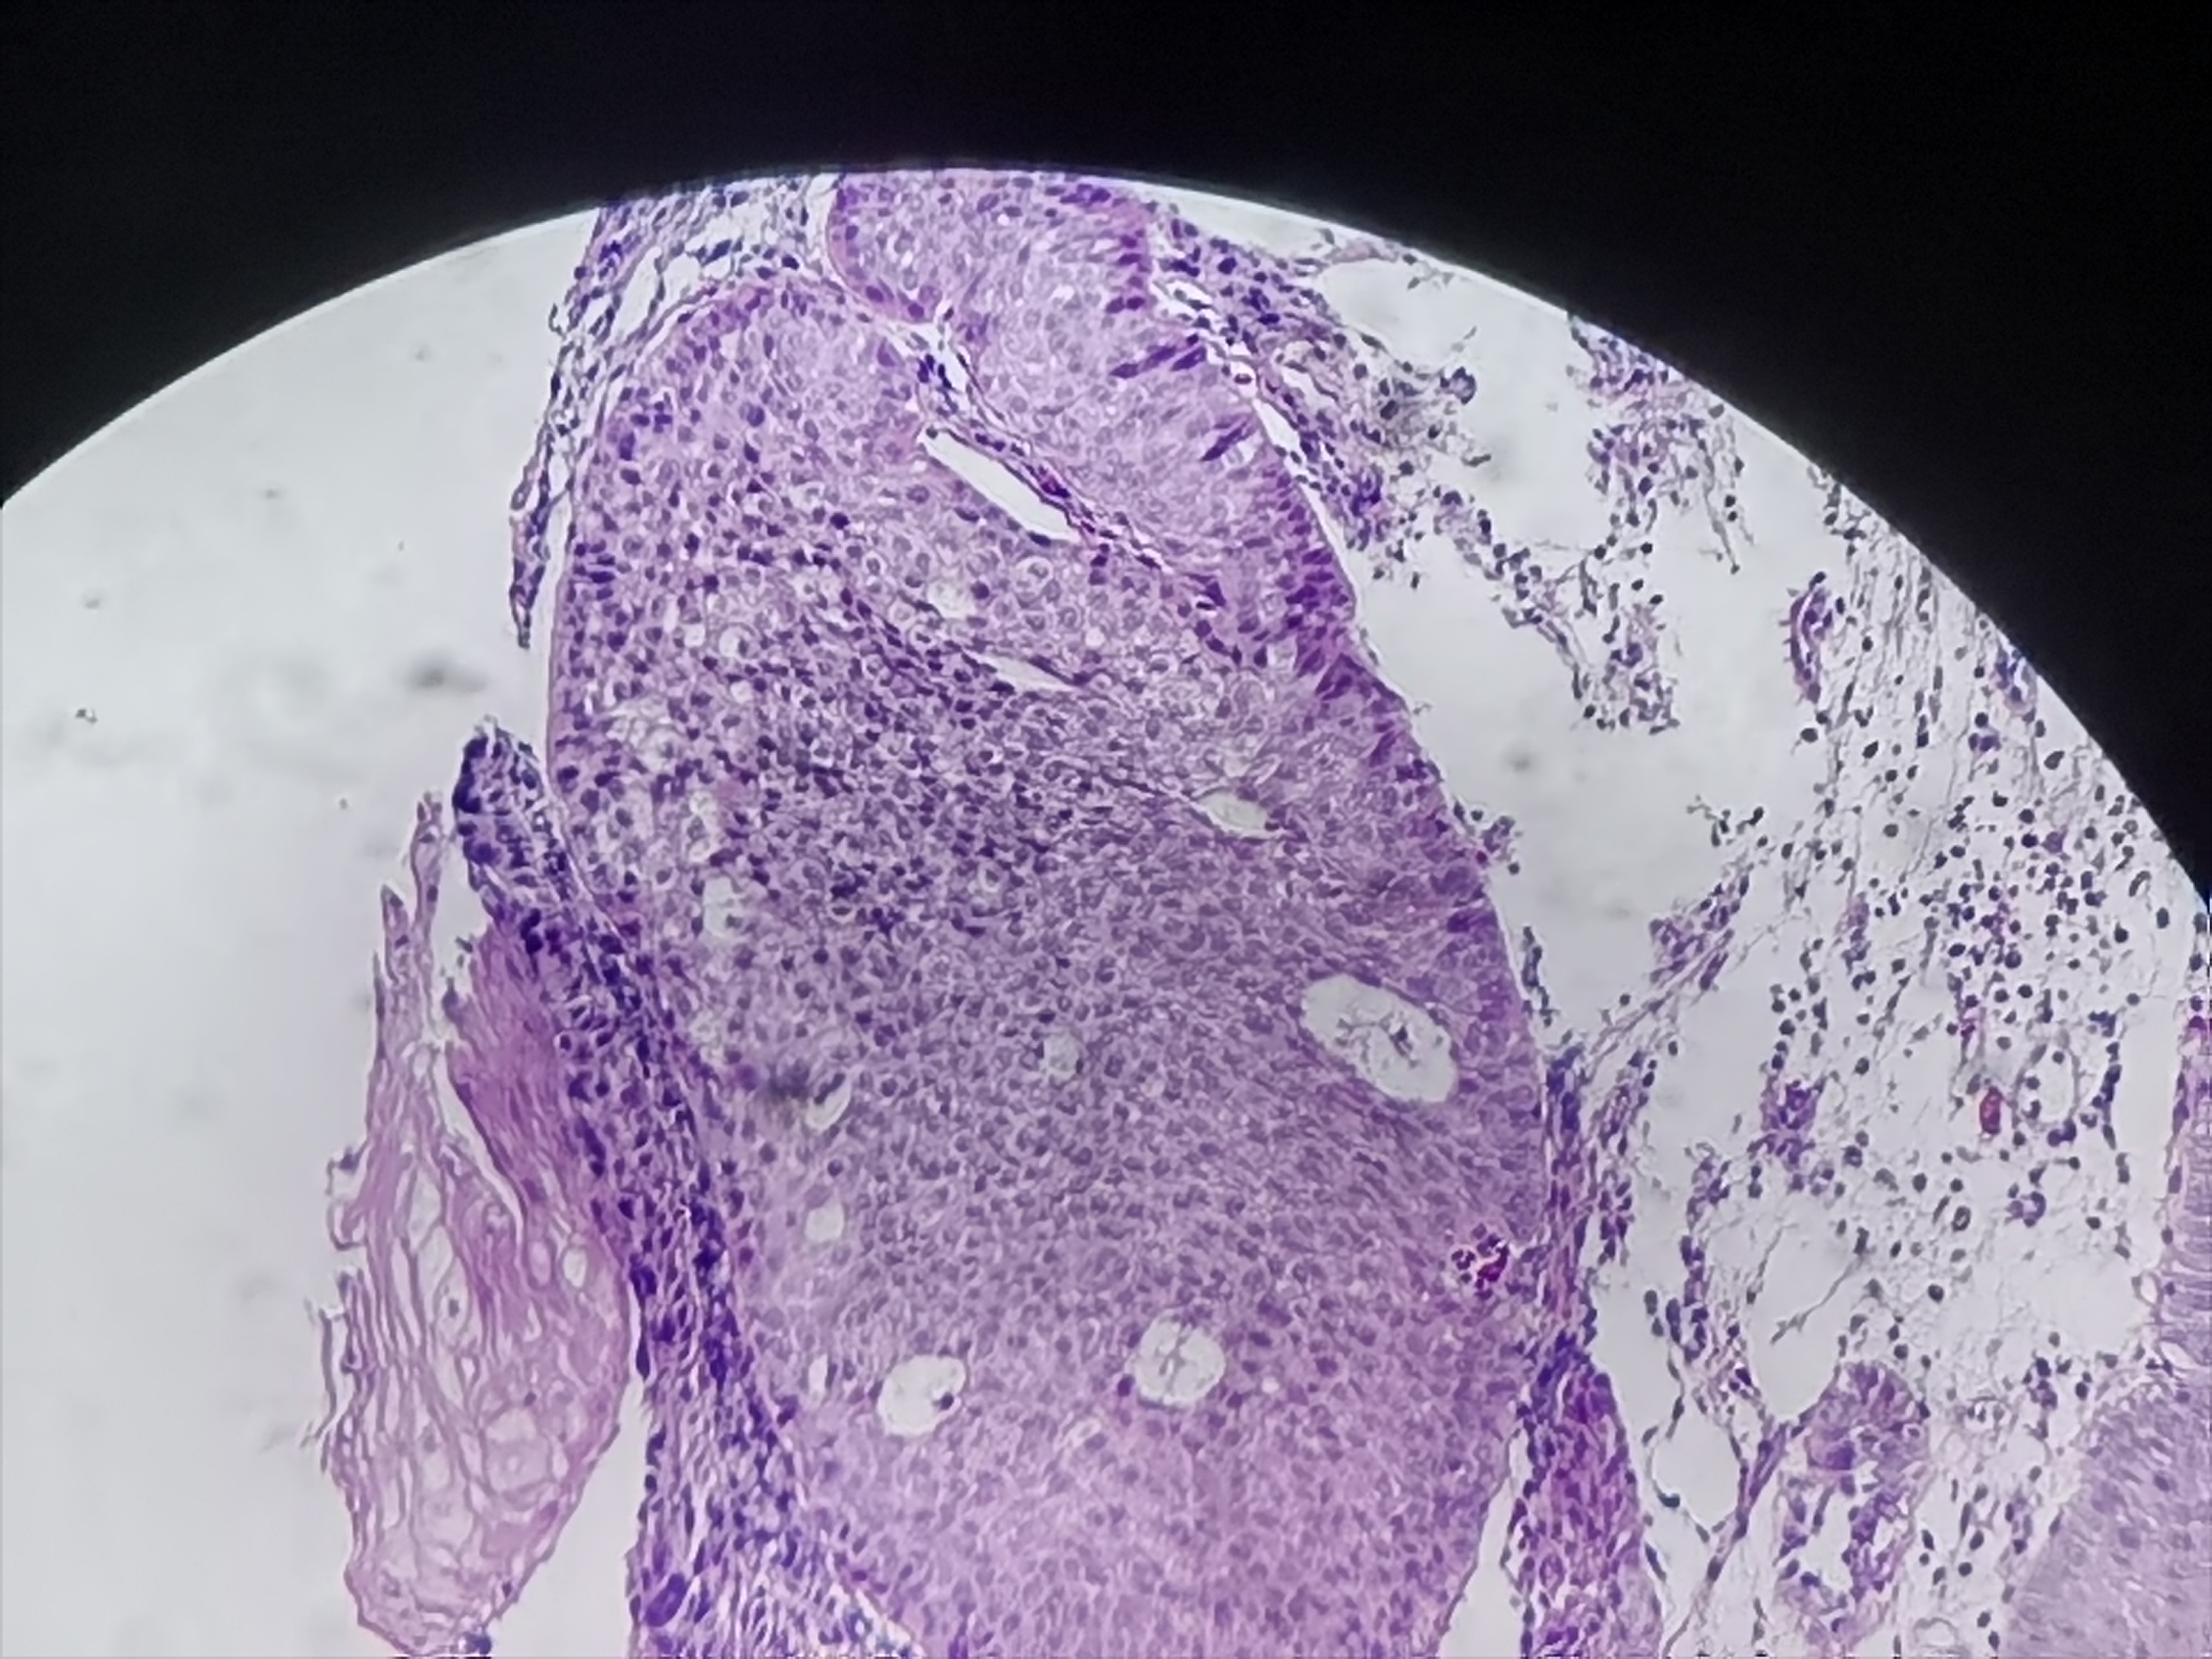

食管活检

性别

男

年龄

61岁

临床诊断

食管癌

一般病史

食管距门齿20cm处可见不规则病灶,质脆,易出血,管腔狭窄,镜子不能通过

标本名称

食管粘膜活检

大体所见

灰白色组织3块

考虑符合:鳞癌